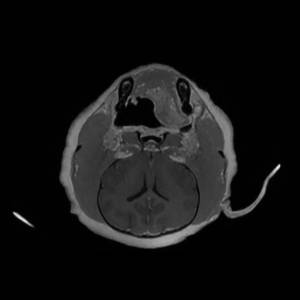

Main Gallery

Playing with a photo gallery function. It is possible to have multiple galleries, each within a namespace.